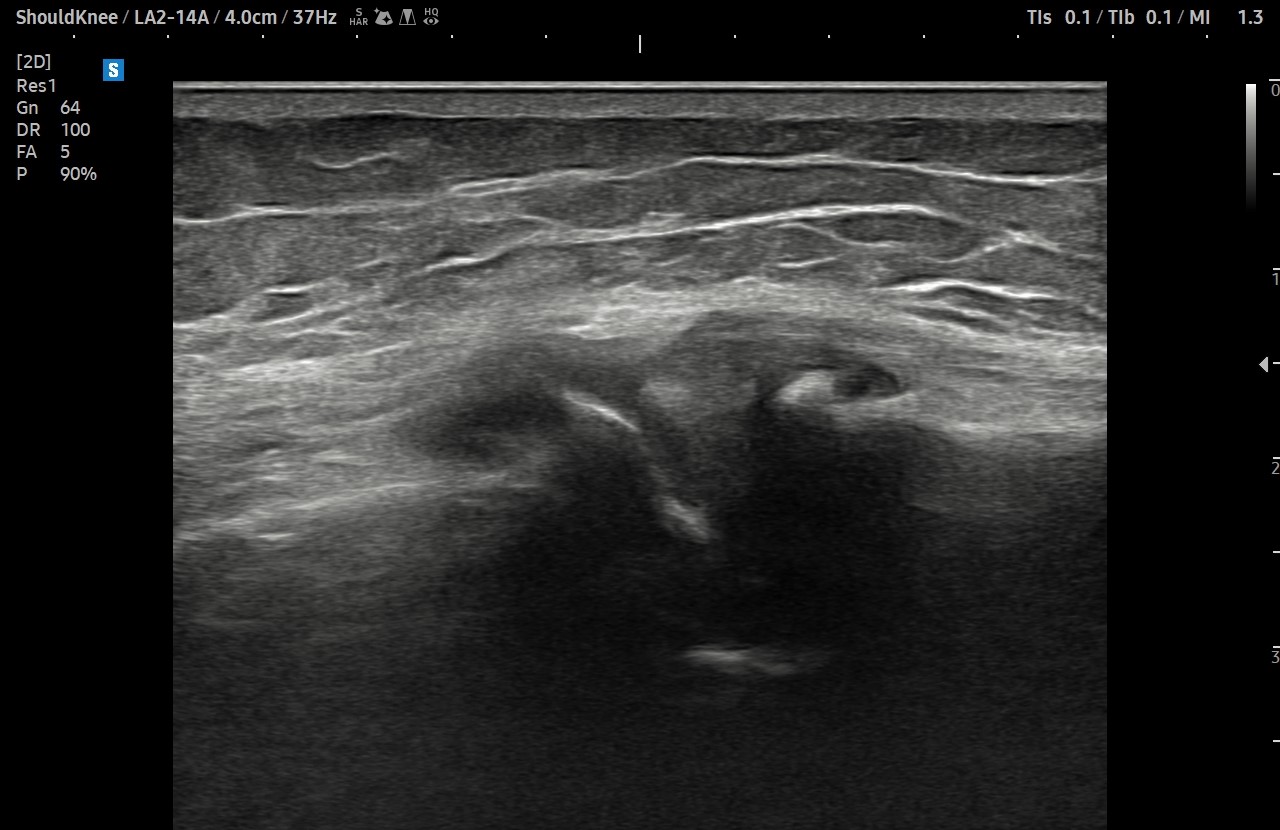

- 치료기간 : 2025. 7 . 4 ~ 2025 . 9 .1

- 치료횟수 : 10 회 (2cycle)

치료 전

치료 후